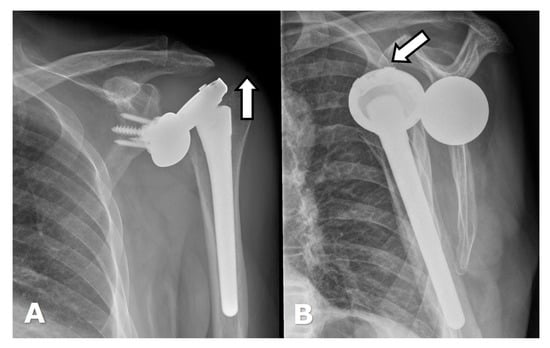

4.3. Unique Complications

5.2. Reverse Arthroplasty

Reverse Total Shoulder Arthroplasty (RTSA)